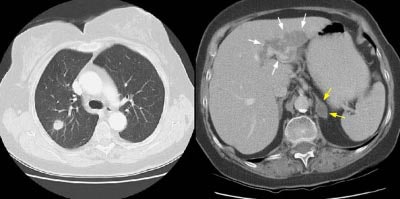

The patient below had an adenocarcinoma in the left lung that was obstructing the left upper lobe bronchus (left image upper row). The staging CT scan demonstrated a large liver cyst (*) and some underlying hepatic heterogeneity best appreciated on liver windows (yellow arrows). The patient had slightly elevated liver function tests, and the findings were felt to be most likely related to areas of sparing in a patient with some hepatic fatty infiltration. Because the possibility of metastatic disease could not be excluded, an MRI of the liver was performed. The heavily T2-weighed image shown (right image bottom row) revealed multiple liver metastases, many of which were not apparent on the contrast-enhanced CT scan (white arrows). MR imaging has been shown to be more sensitive for detecting liver metastases when compared to CT.

NOTE: Click image to enlarge